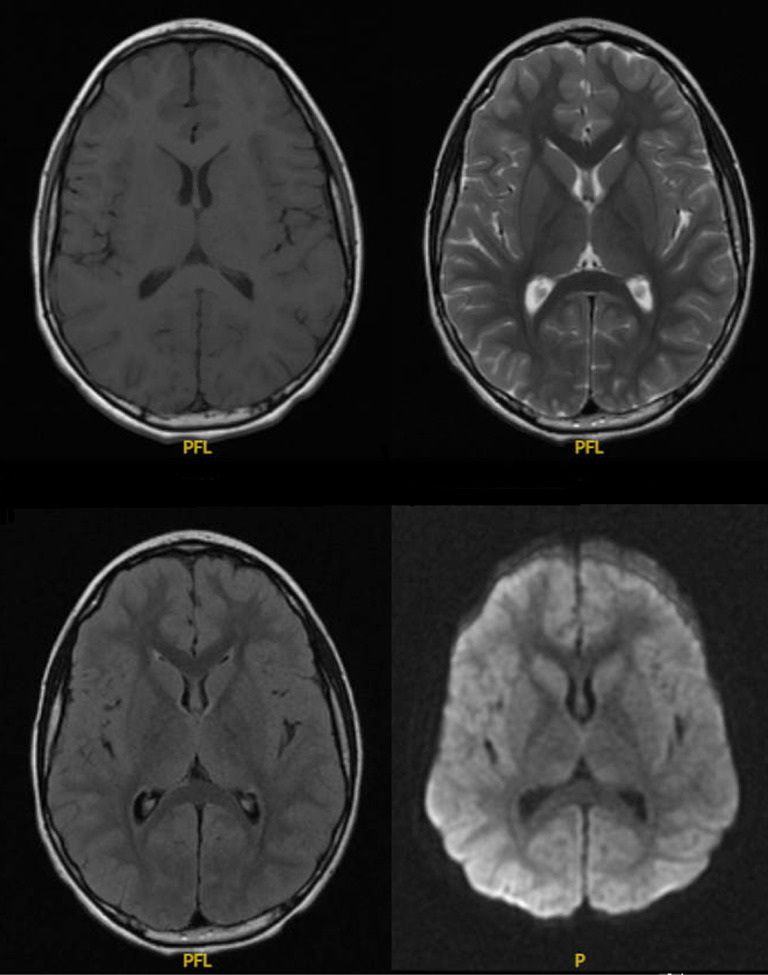

慢性炎症性脱髓鞘多神经病变(CIDP)后的病毒感染和流感疫苗接种已得到充分证明。然而,目前还没有证实的自然甲型流感感染导致CIDP的发展。因此,我们提出的情况下,6岁的男性谁开发CIDP后确诊甲型流感感染。患者最初表现为典型的流感样症状,大约1个月后逐渐出现步态不稳定和腿部无力。尽管在诊断为格林-巴-罗综合征后静脉注射免疫球蛋白治疗最初有所改善,但他的症状复发,包括下肢无力、大小便失禁和感觉丧失。肌电图证实脱髓鞘性多神经病变,诊断为CIDP。

Chronic inflammatory demyelinating polyneuropathy (CIDP) following viral infections and influenza vaccination has been well documented. However, there have been no confirmed natural influenza A infections leading to development of CIDP. Therefore, we present the case of a 6-year-old male who developed CIDP following a confirmed influenza A infection. Initially presenting with typical flu-like symptoms, the patient experienced a gradual onset of gait instability and leg weakness approximately 1 month later. Despite initial improvement with intravenous immunoglobulin therapy following a diagnosis of Guillain-Barré syndrome, his symptoms relapsed, including lower extremity weakness, incontinence, and sensory loss. Electromyography confirmed a demyelinating polyneuropathy, leading to a diagnosis of CIDP.